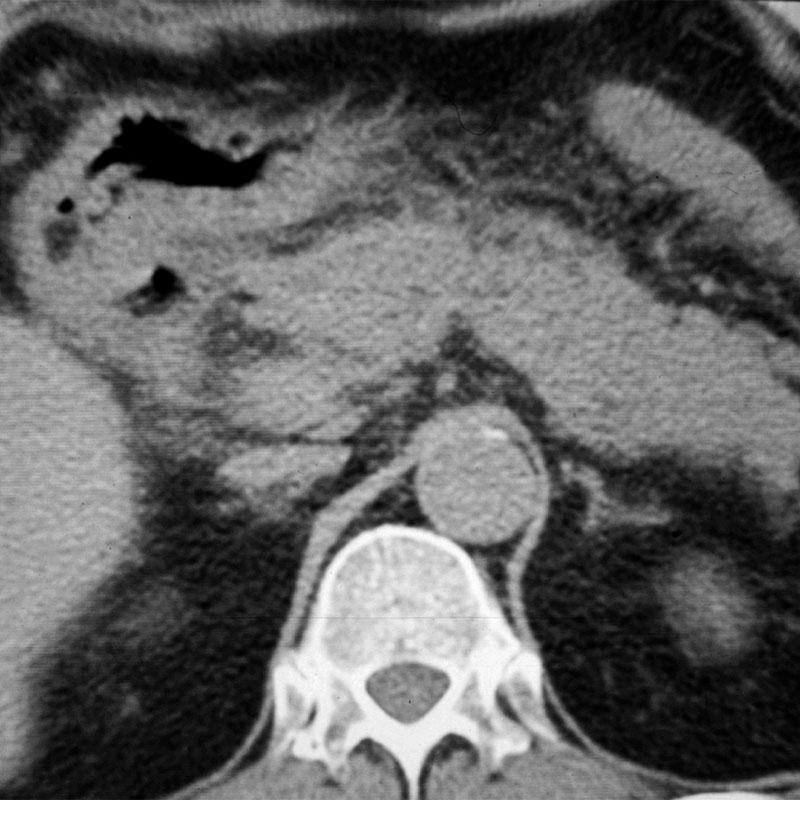

Their US apperarences include mostly an inhomogeneous, hyperechoic or hypoechoic lesion, which is arterially hypervascularised, and several arterioportal shunts may develop. The demonstration of shunt related portal vein flow disturbance by doppler US has a prominent importance. The adjudication of the cirrhosis related HCC by ultrasound is often a particularly difficult task.

HCC appears mostly as low density on the native CT scan, with inhomogeneous structure and a sorrounding with a slightly increased density bearing capsule can be also detected. The completion of the three-phase CT scan (arterial, venous, late) is especially important in case of a suspicion of HCC. The appearance of the inhomogeneous lesion in the arterial phase, including sometimes non contrast enhancing necrotic areas inside, bears with a diagnostic value. The capsule can be detected best in the venous phase.

Concerning the HCC, the knowledge of history is very important for the decision and usually the oncoteams consider the performance of an imaging modality guided biopsy basically important for the further therapeutic decisions (because of the hystological validation rather core biopsy should be performed! (Figure 26, 27, 28).

Figure 26: HCC, verified with FNAB, US

Figure 27: HCC, TAE, agniography

Figure 28: HCC, native CT after TAE